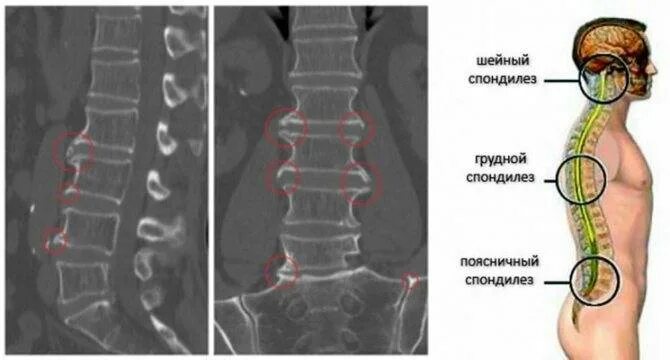

Деформирующий спондилез спондилоартроз